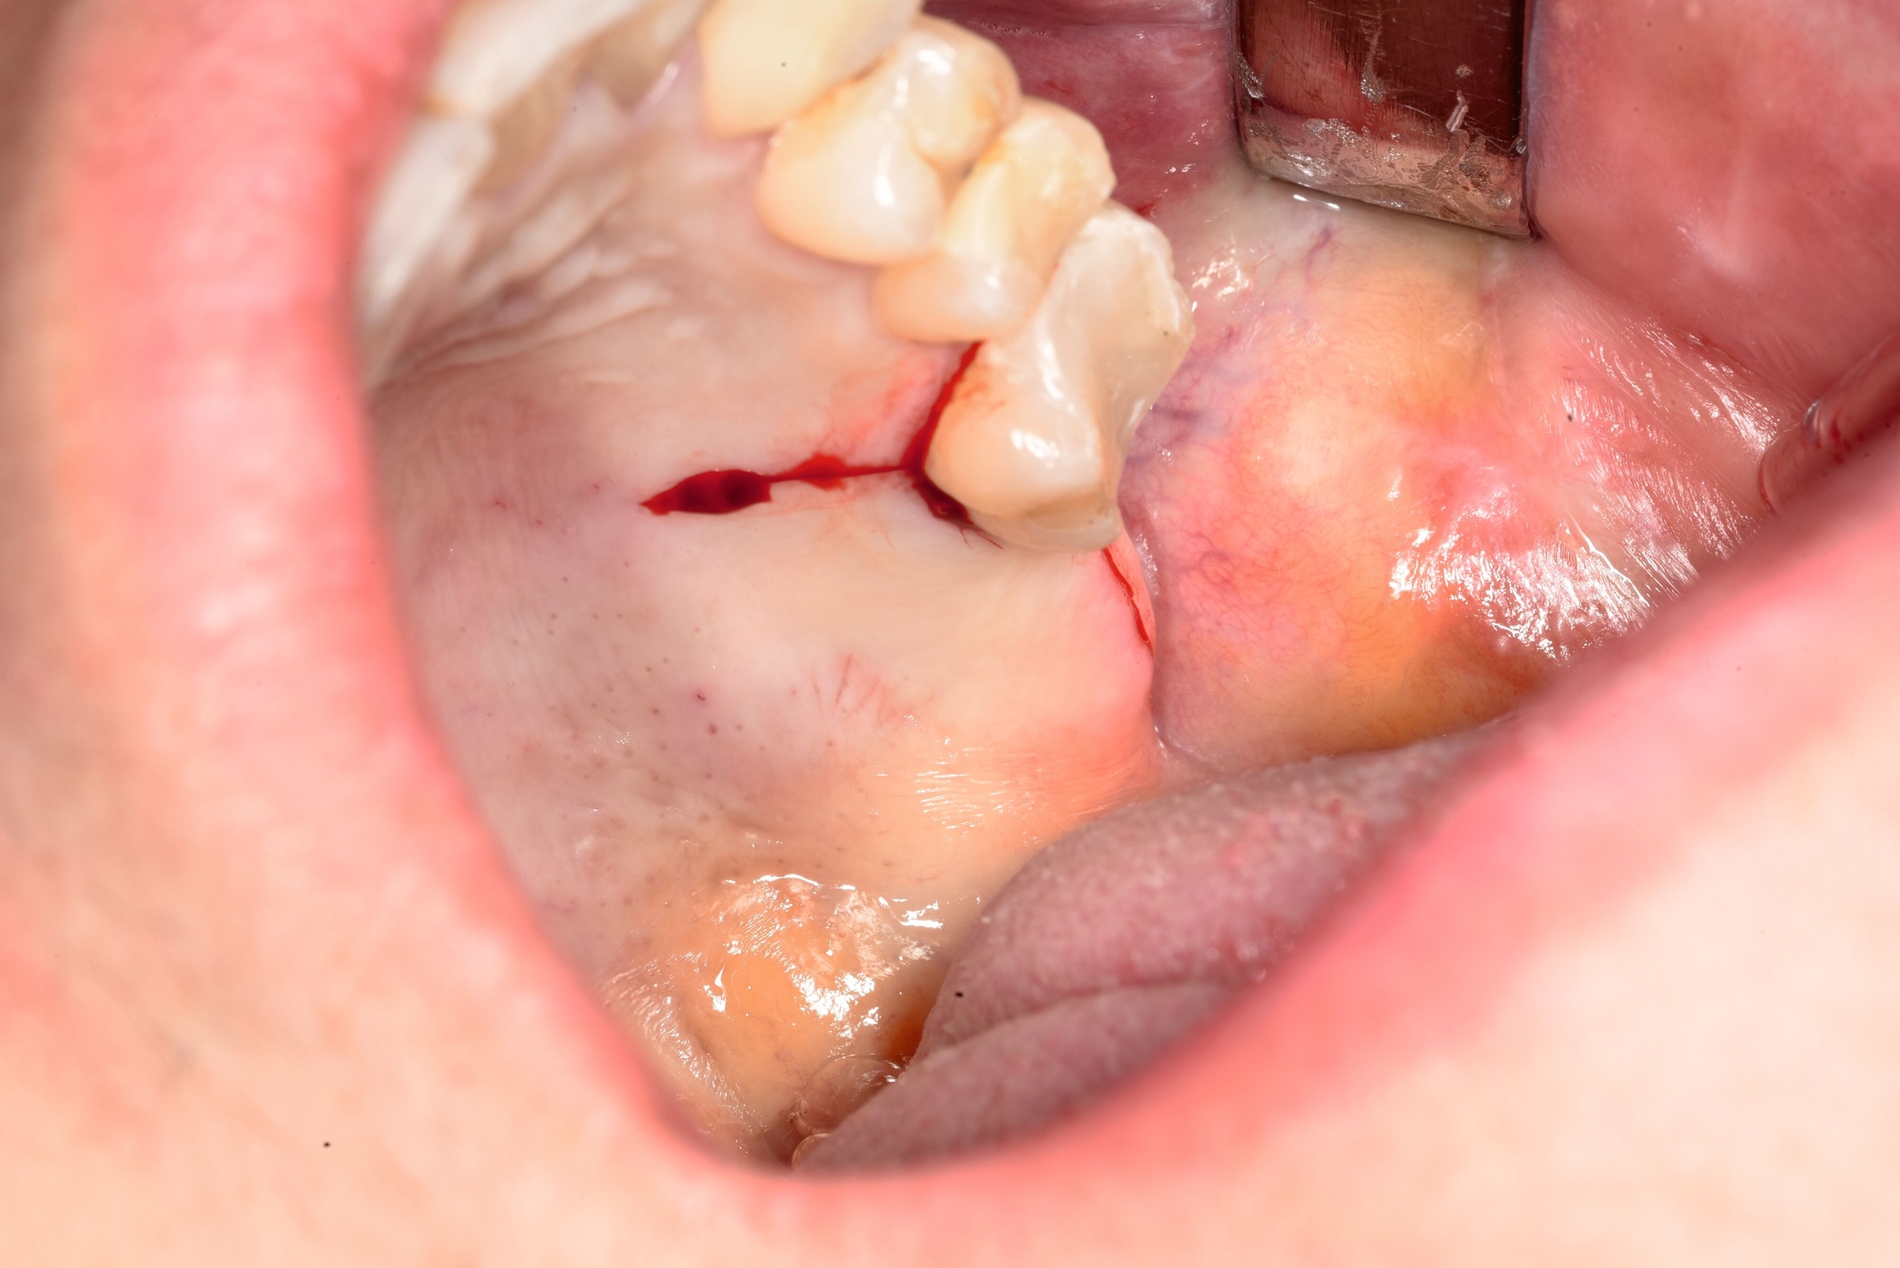

Der Zugangsweg wurde palatinal gewählt. Nach systemgerechter Kalibrierung erfolgte zunächst eine navigationsgestützte Orientierung, da sich der klinische Situs intraoral komplett reizlos und ohne sichtbare Lagehinweise präsentierte (Abbildung 3). Eine Markierung mit dem Rosenbohrer auf der Schleimhaut diente der exakten Referenz für die Lappenschnittführung (Abbildung 4). Präoperativ wurde zudem eine Verbandsplatte für den Gaumen angefertigt, um die postoperative Stabilisierung zu erleichtern.